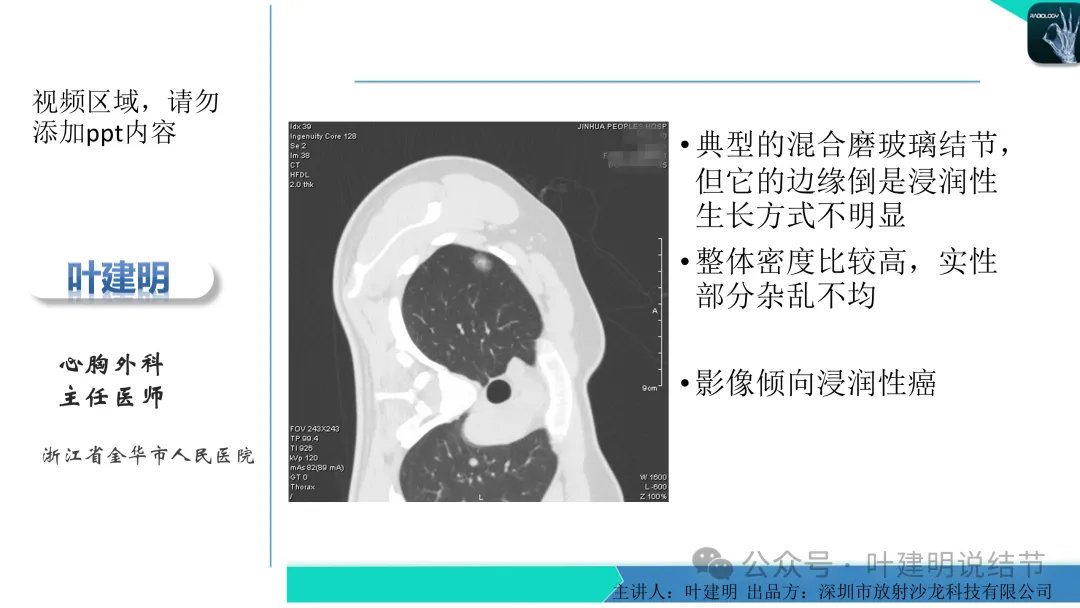

早在2020年时,我受邀在《放射沙龙》做过一个系列的精品课,当时专门总结分析过各类良恶性肺结节与肿块的影像特征,这是当时关于微浸润性腺癌影像特征的分析,今天看来仍基本不太需要改变,大家有兴趣的可以参考: